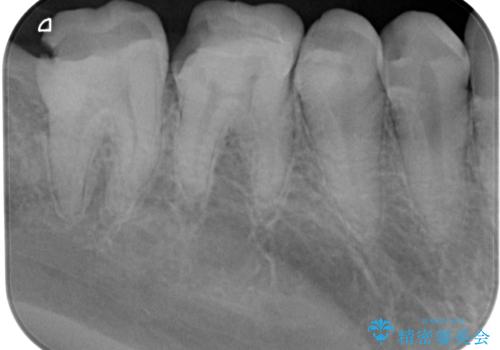

右下の6番目の歯は初診時から詰め物が大きかったため、被せものでの治療を提案していましたが、患者様の強いご希望でセラミックの詰め物(セラミックインレー)での治療をされていました。今回メインテナンス時に来院されたときに被せもの(オールセラミッククラウン)での治療を再度提案させていただき、患者様にも納得をしていただいたうえで、オールセラミッククラウンによる治療を行いました。

拡大鏡視野下で、セラミックの詰め物(セラミックインレー)、虫歯の除去を行い、オールセラミッククラウンに適した形に整えました。

歯と歯茎の間に圧排糸と言われる糸を入れてシリコーン印象材にて型どりをしました。